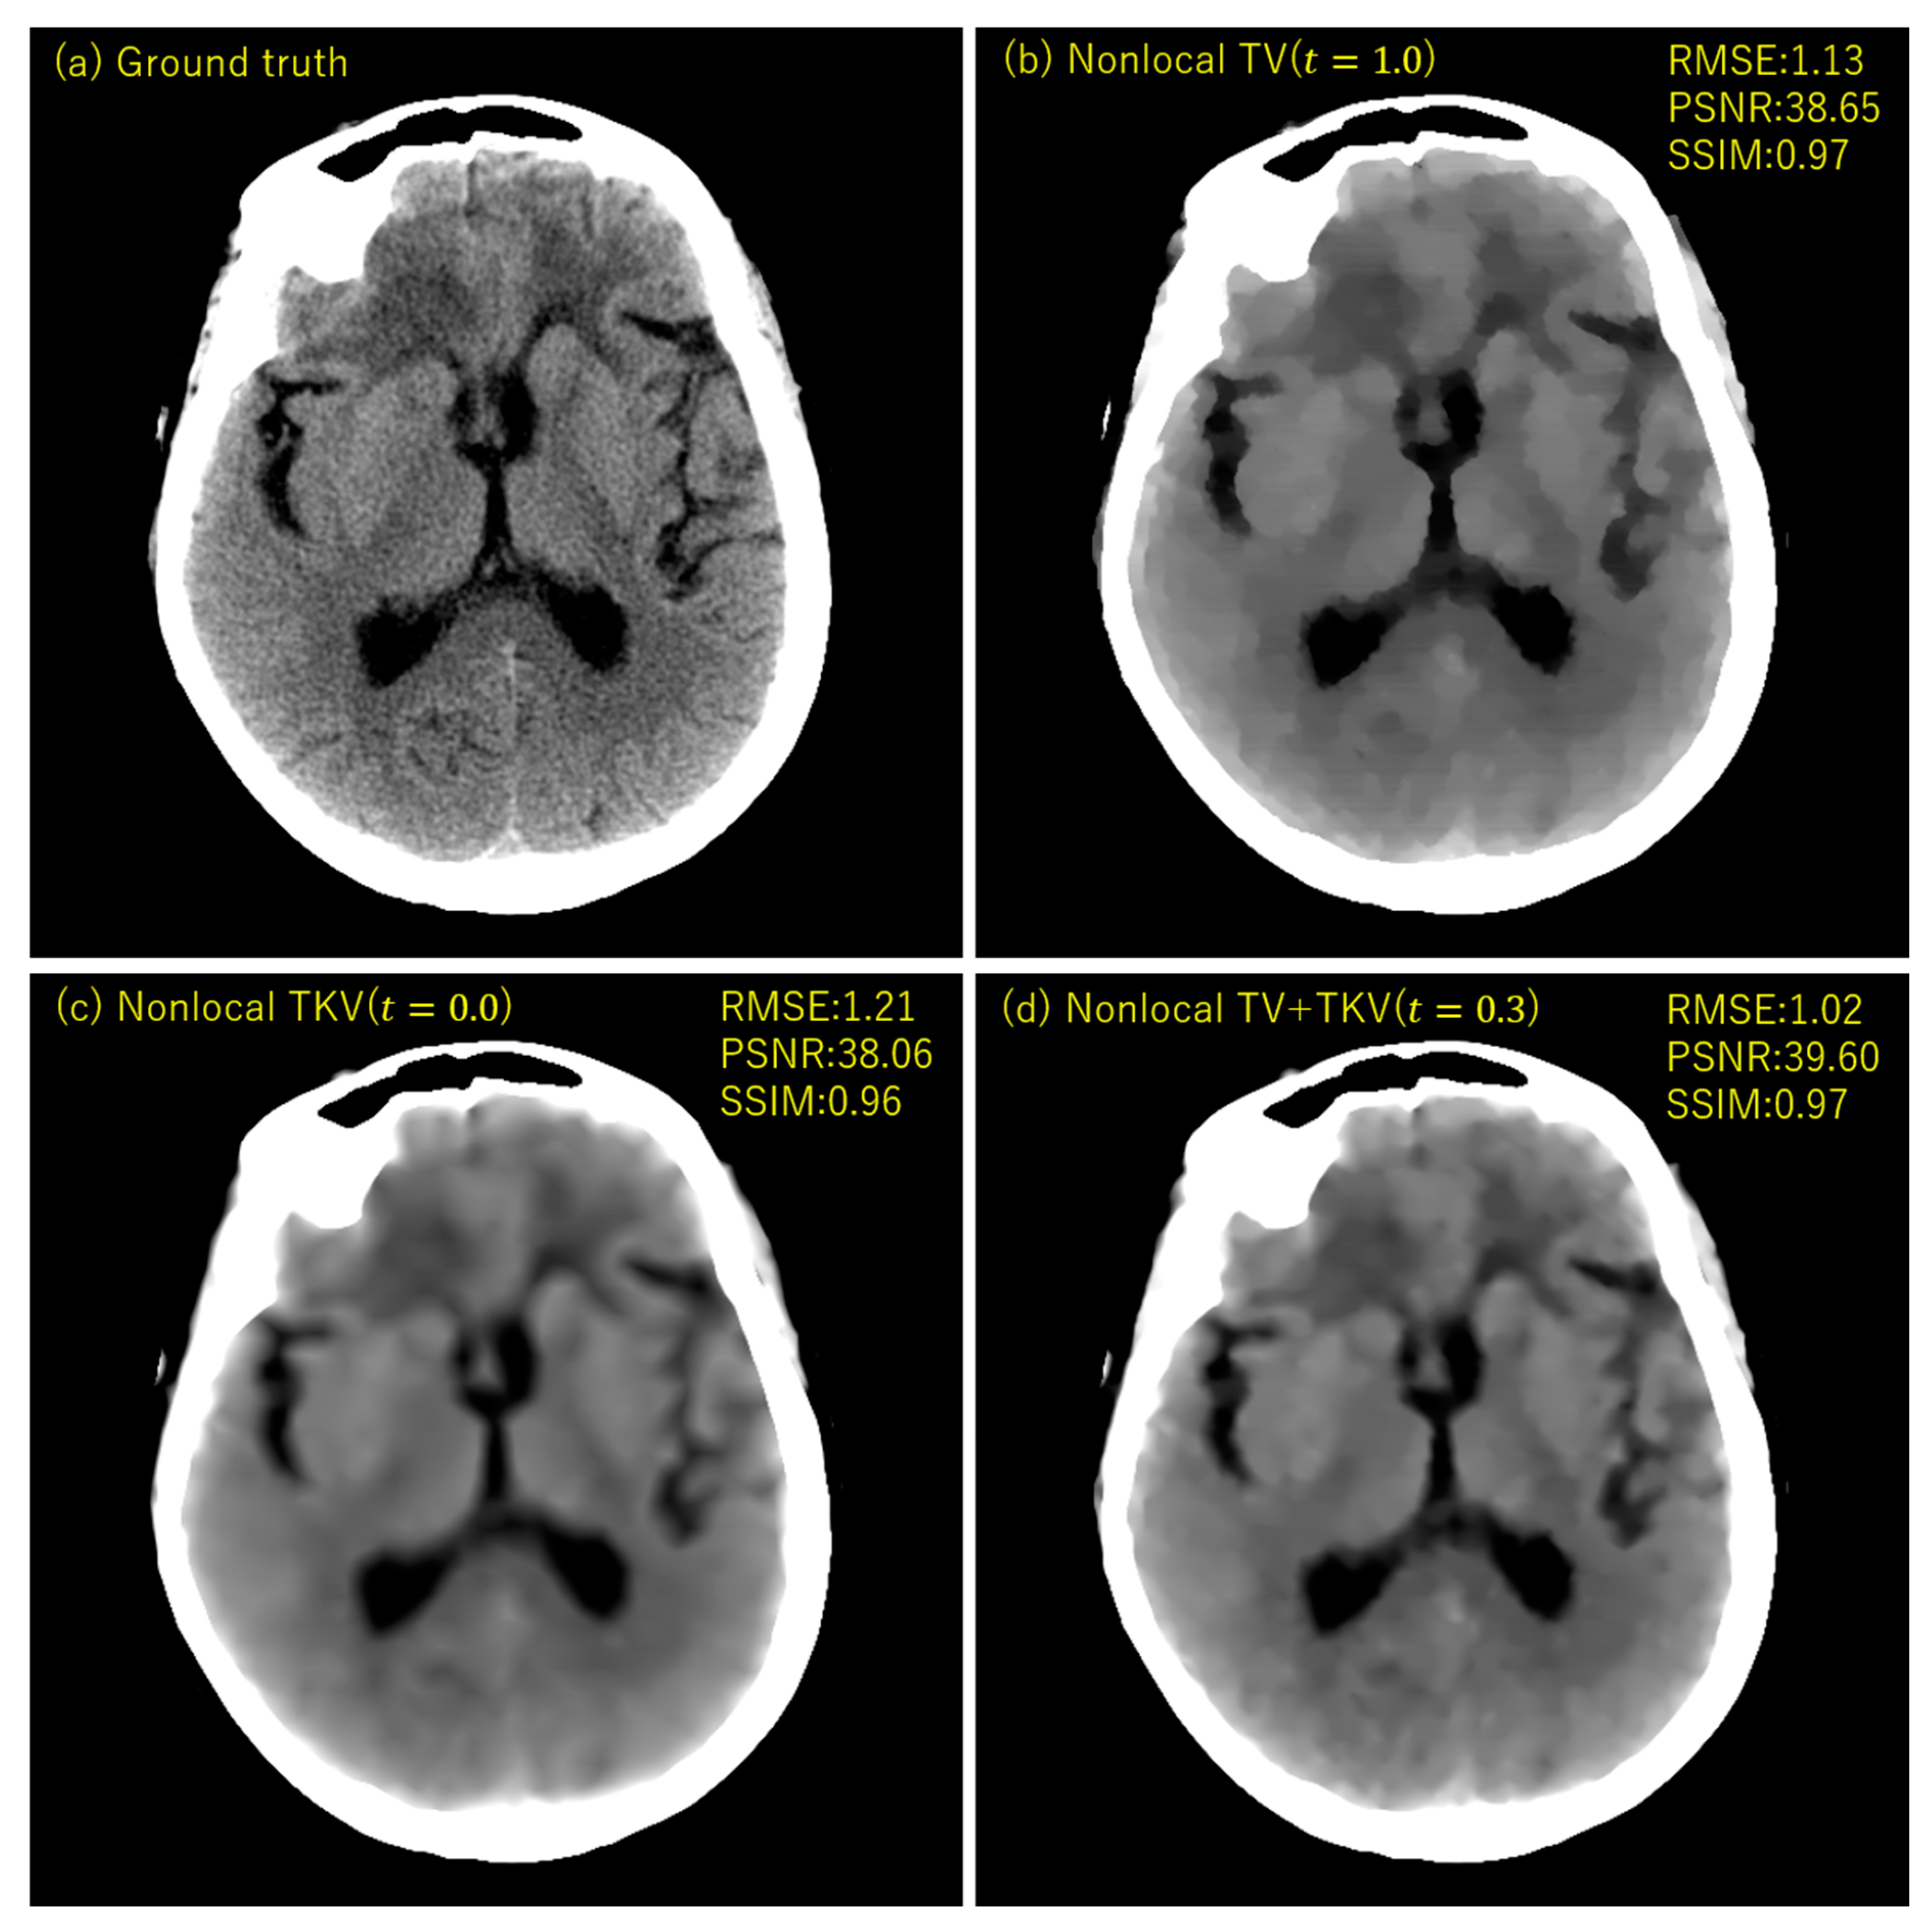

3. Experimental Results

4. Discussion